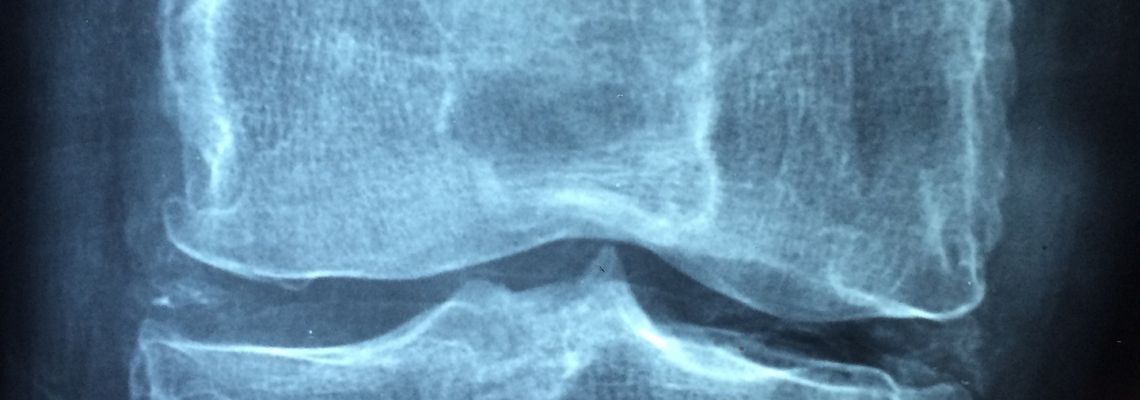

Het verschil tussen artritis en artrose

Artritis is een ontsteking van de gewrichten, onder meer veroorzaakt door reumatische aandoeningen (bijvoorbeeld reumatoïde artritis), verwondingen of bacteriële infectie (septische artritis).

De bekendste symptomen zijn hevige pijn bij belasting en beweging van het aangetaste gewricht. Soms leidt artritis ook tot een uitgesproken zwelling met roodheid of algemene symptomen zoals koorts. Bij artritis wordt ontstekingsvocht in plaats van gewrichtsvocht gevormd, waardoor de smering en de voeding van het gewrichtskraakbeen gestoord raakt.

Artrose

Artritis is niet hetzelfde als artrose. Hierbij wordt de pijn in de gewrichten veroorzaakt wordt door mechanische slijtage van het kraakbeen.